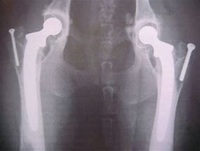

D. Total Hip Replacement (THR)

Best for: Large-breed dogs with severe hip dysplasia.

Procedure: Replaces the hip joint with a prosthetic implant.

Outcome: Restores full mobility and eliminates pain.

Total Hip Replacement (THR) is a surgical procedure used to treat severe hip dysplasia, arthritis, or chronic hip pain in dogs. The procedure involves:

Removing the damaged hip joint

Replacing it with an artificial hip implant

Restoring pain-free movement and normal joint function

THR is the gold standard for treating advanced hip disease, allowing dogs to regain full range of motion and return to an active lifestyle.

THR involves replacing both the femoral head (ball) and acetabulum (socket) with prosthetic components made of metal and plastic.